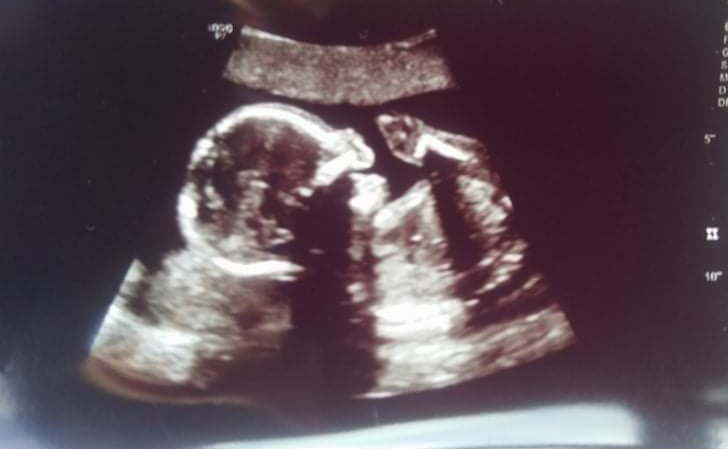

Минавам да се похваля.😆 Бях на ЖК, бебето е вече 387гр , в 19гс. Плацентата ми вече се е вдигнала и спирам утрогестана ❤️ Пуснахме микробиология и антитела. Абе щастливо ми е 💙 и даже болката в крака от обаждащата се дископатия не може да помрачи усмивката ми